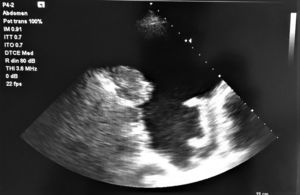

Las masas malignas de la pleura incluyen el mesotelioma, el linfoma y las metástasis. Ecográficamente podemos visualizar un engrosamiento irregular, a veces nodular, asociado a importante derrame pleural (fig. 1), caracteriza el mesotelioma pleural maligno, como posteriormente se identificó en el estudio histológico1.